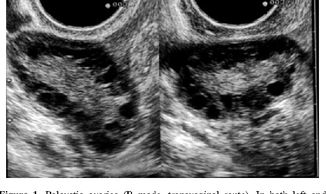

Polycystic ovarian syndrome (PCOS) may cause irregular menses and contribute to infertility. In clinical practice, 75% of women with PCOS suffer from anovulation infertility and 50% of them experience recurrent pregnancy loss. It is, however, not clear whether these defects are caused by uterine dysfunction itself or by the interrupted interaction between uterine cells and the developing embryo.

Polycystic Ovarian syndrome (PCOS)